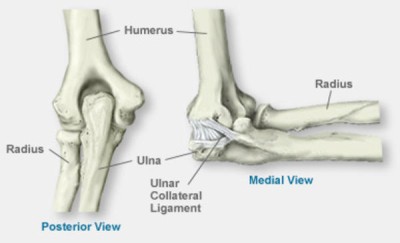

The most uncommon form of mental illness on this list is known as Mietens-Weber Syndrome. It is a hereditary illness that can cause mild to moderate mental impairments, as well as dislocated and/or contracted elbows.

Other symptoms may include a shortened or contracted elbow. This far, there have only been nine cases reported.